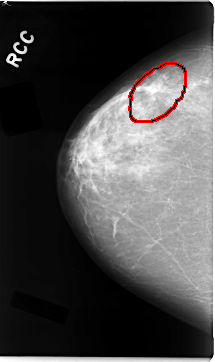

C_0034_1.RIGHT_CC

FILE: C_0034_1.RIGHT_CC.OVERLAY

TOTAL_ABNORMALITIES 1

ABNORMALITY 1

LESION_TYPE MASS SHAPE IRREGULAR MARGINS SPICULATED

ASSESSMENT 5

SUBTLETY 5

PATHOLOGY MALIGNANT

TOTAL_OUTLINES 1

BOUNDARY